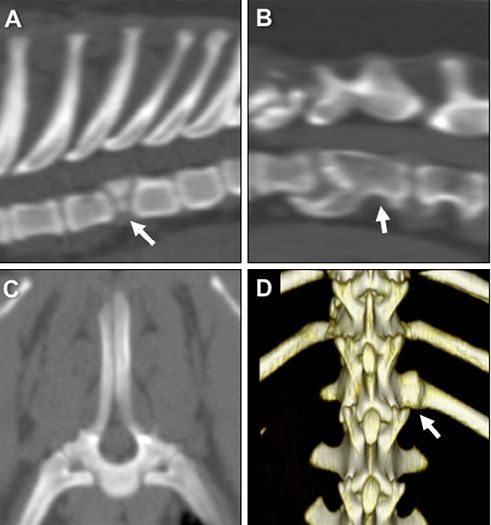

椎体疾病:本身短腿品种的犬,出现IVDD(椎间盘退化性疾病)的概率就会高一些,短头品种犬(法斗、英斗、八哥)很多椎体本身也是畸形的,包括椎体桥连、半椎体、移行椎、脊柱裂等。2011年Moissonnier认为半椎体在螺旋尾的法斗中更容易出现,病变位置多数是在胸椎。2017年Rechard等人通过回顾性研究发现虽然很多法斗都会出现单个或者多个椎体的发育异常,但是因为这些异常导致神经症状的还是比较少的(作者发现在CT或者X光下可见的异常椎体病历中,约有78%是没有临床症状的),但是八哥和法斗在这点上就有区别,八哥如果有椎体的发育异常,出现神经症状的概率就大一些。如果出现神经症状的法斗同时有IVDD和胸椎椎体发育异常,那么造成临床症状的主要原因更考虑是IVDD而不是椎体的发育异常。

A-D分别是半椎体、椎体桥连、脊柱裂、移形椎